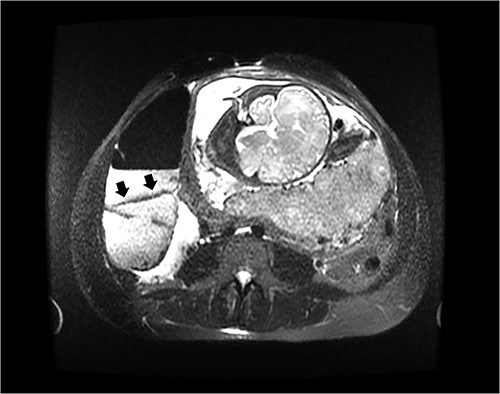

On hospital day 2, the patient became obstipated, and her abdominal exam had notable distension with persistent right upper quadrant tenderness. An abdominal magnetic resonance imaging (MRI) was performed revealing dilated small intestine with air-fluid levels and an inverted-appearing, prominent cecum (Figs. 1 and 2). The patient was diagnosed with an acute abdomen from probable cecal volvulus versus appendicitis and was urgently taken to the operating room for cesarean section (c-section) to facilitate abdominal exploration. After delivery of the child, a cecal bascule was found, with a severely distended cecum (Fig. 3). Because the cecum and ascending colon were deserosalized, a right hemicolectomy with primary ileocolic anastomosis was performed. The patient had return of bowel function on post operative day 5 and was discharged home on day 7.

Coronal image of the same MRI showing a dilated cecum displaced superiorly, consistent with a cecal bascule.